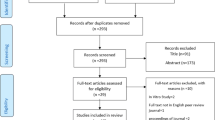

An electronic literature search was performed in the PubMed interface of Medline (National Library of Medicine), Scopus Database, and Web of Science to identify as many articles as possible that applied FD analysis in the assessment of skeletal BMD using dental imaging modalities up to February 2014. The inclusion criteria used for the initial selection of appropriate articles from the published abstracts consisted of combinations of the following keywords: (1) fractal and bone mineral density, (2) fractal and osteoporosis, (3) fractal and jaws, and (4) fractal and mandibular. The initial eligibility of potential studies was determined by reading the title and abstract of each article identified by the search engine using the criteria mentioned above. All articles that appeared to meet the inclusion criteria based on their abstracts were selected and collected. The first electronic search resulted in 204 different abstracts. The final selection was completed after eliminating duplicated articles, reviews of the literature, and articles that were not related to osteoporosis and FD analysis of the jaws. Figure 1 shows a flowchart of the study selection procedure.

After a complete analysis of the articles, only 14 articles met all of the inclusion criteria [24–37]. One article contained two different experiments, and was thus considered as two different studies [24]. The study designs, objectives, main results, and conclusions related to the FD are shown in Table 1. Table 2 shows the technical parameters of the FD calculations in the selected articles. Reading of the selected articles further demonstrated that the sizes and locations of the regions of interest (ROIs) were not standardized, as can be seen in Fig. 2.